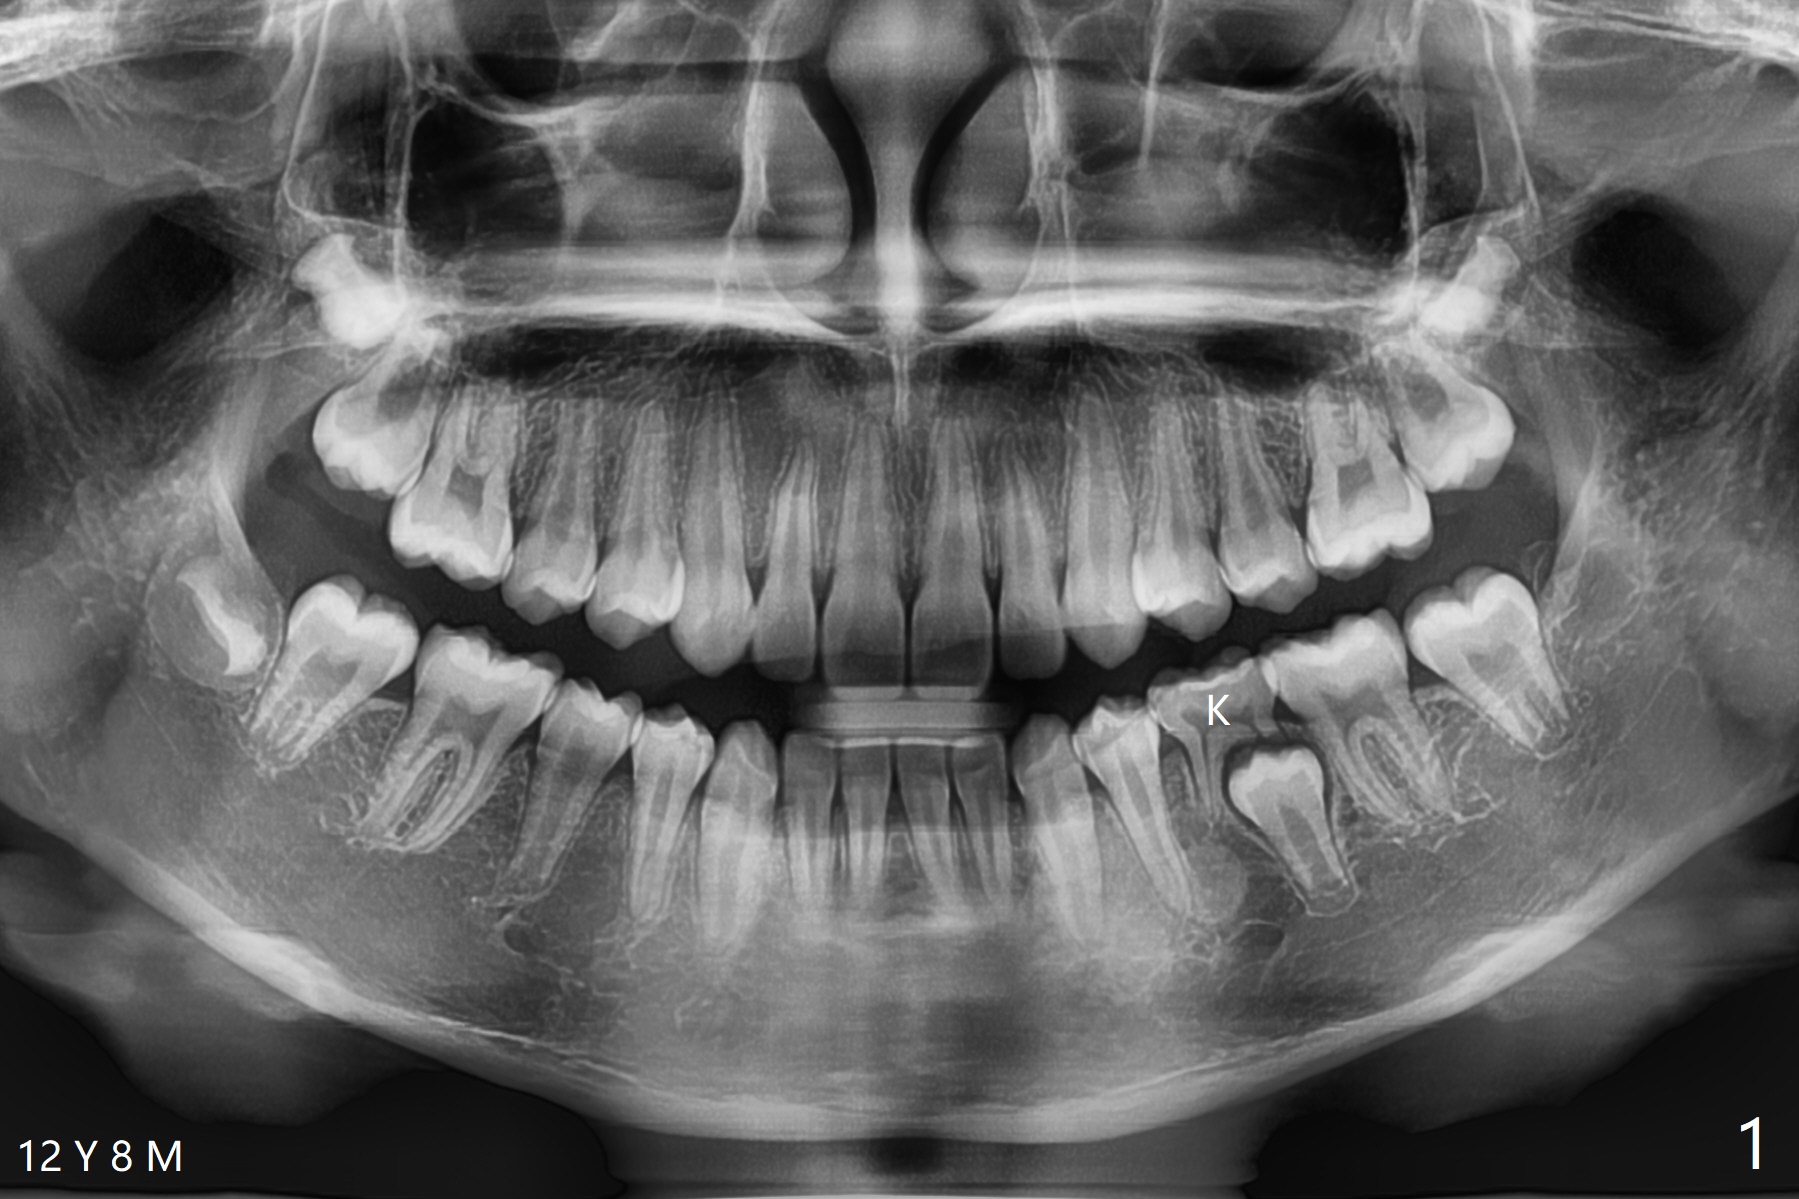

Delayed Eruption of #20

A 12-year-8-month-old woman retains K (Fig.1). Four months post extraction of K, the underlying permanent tooth is going to erupt (Fig.2).